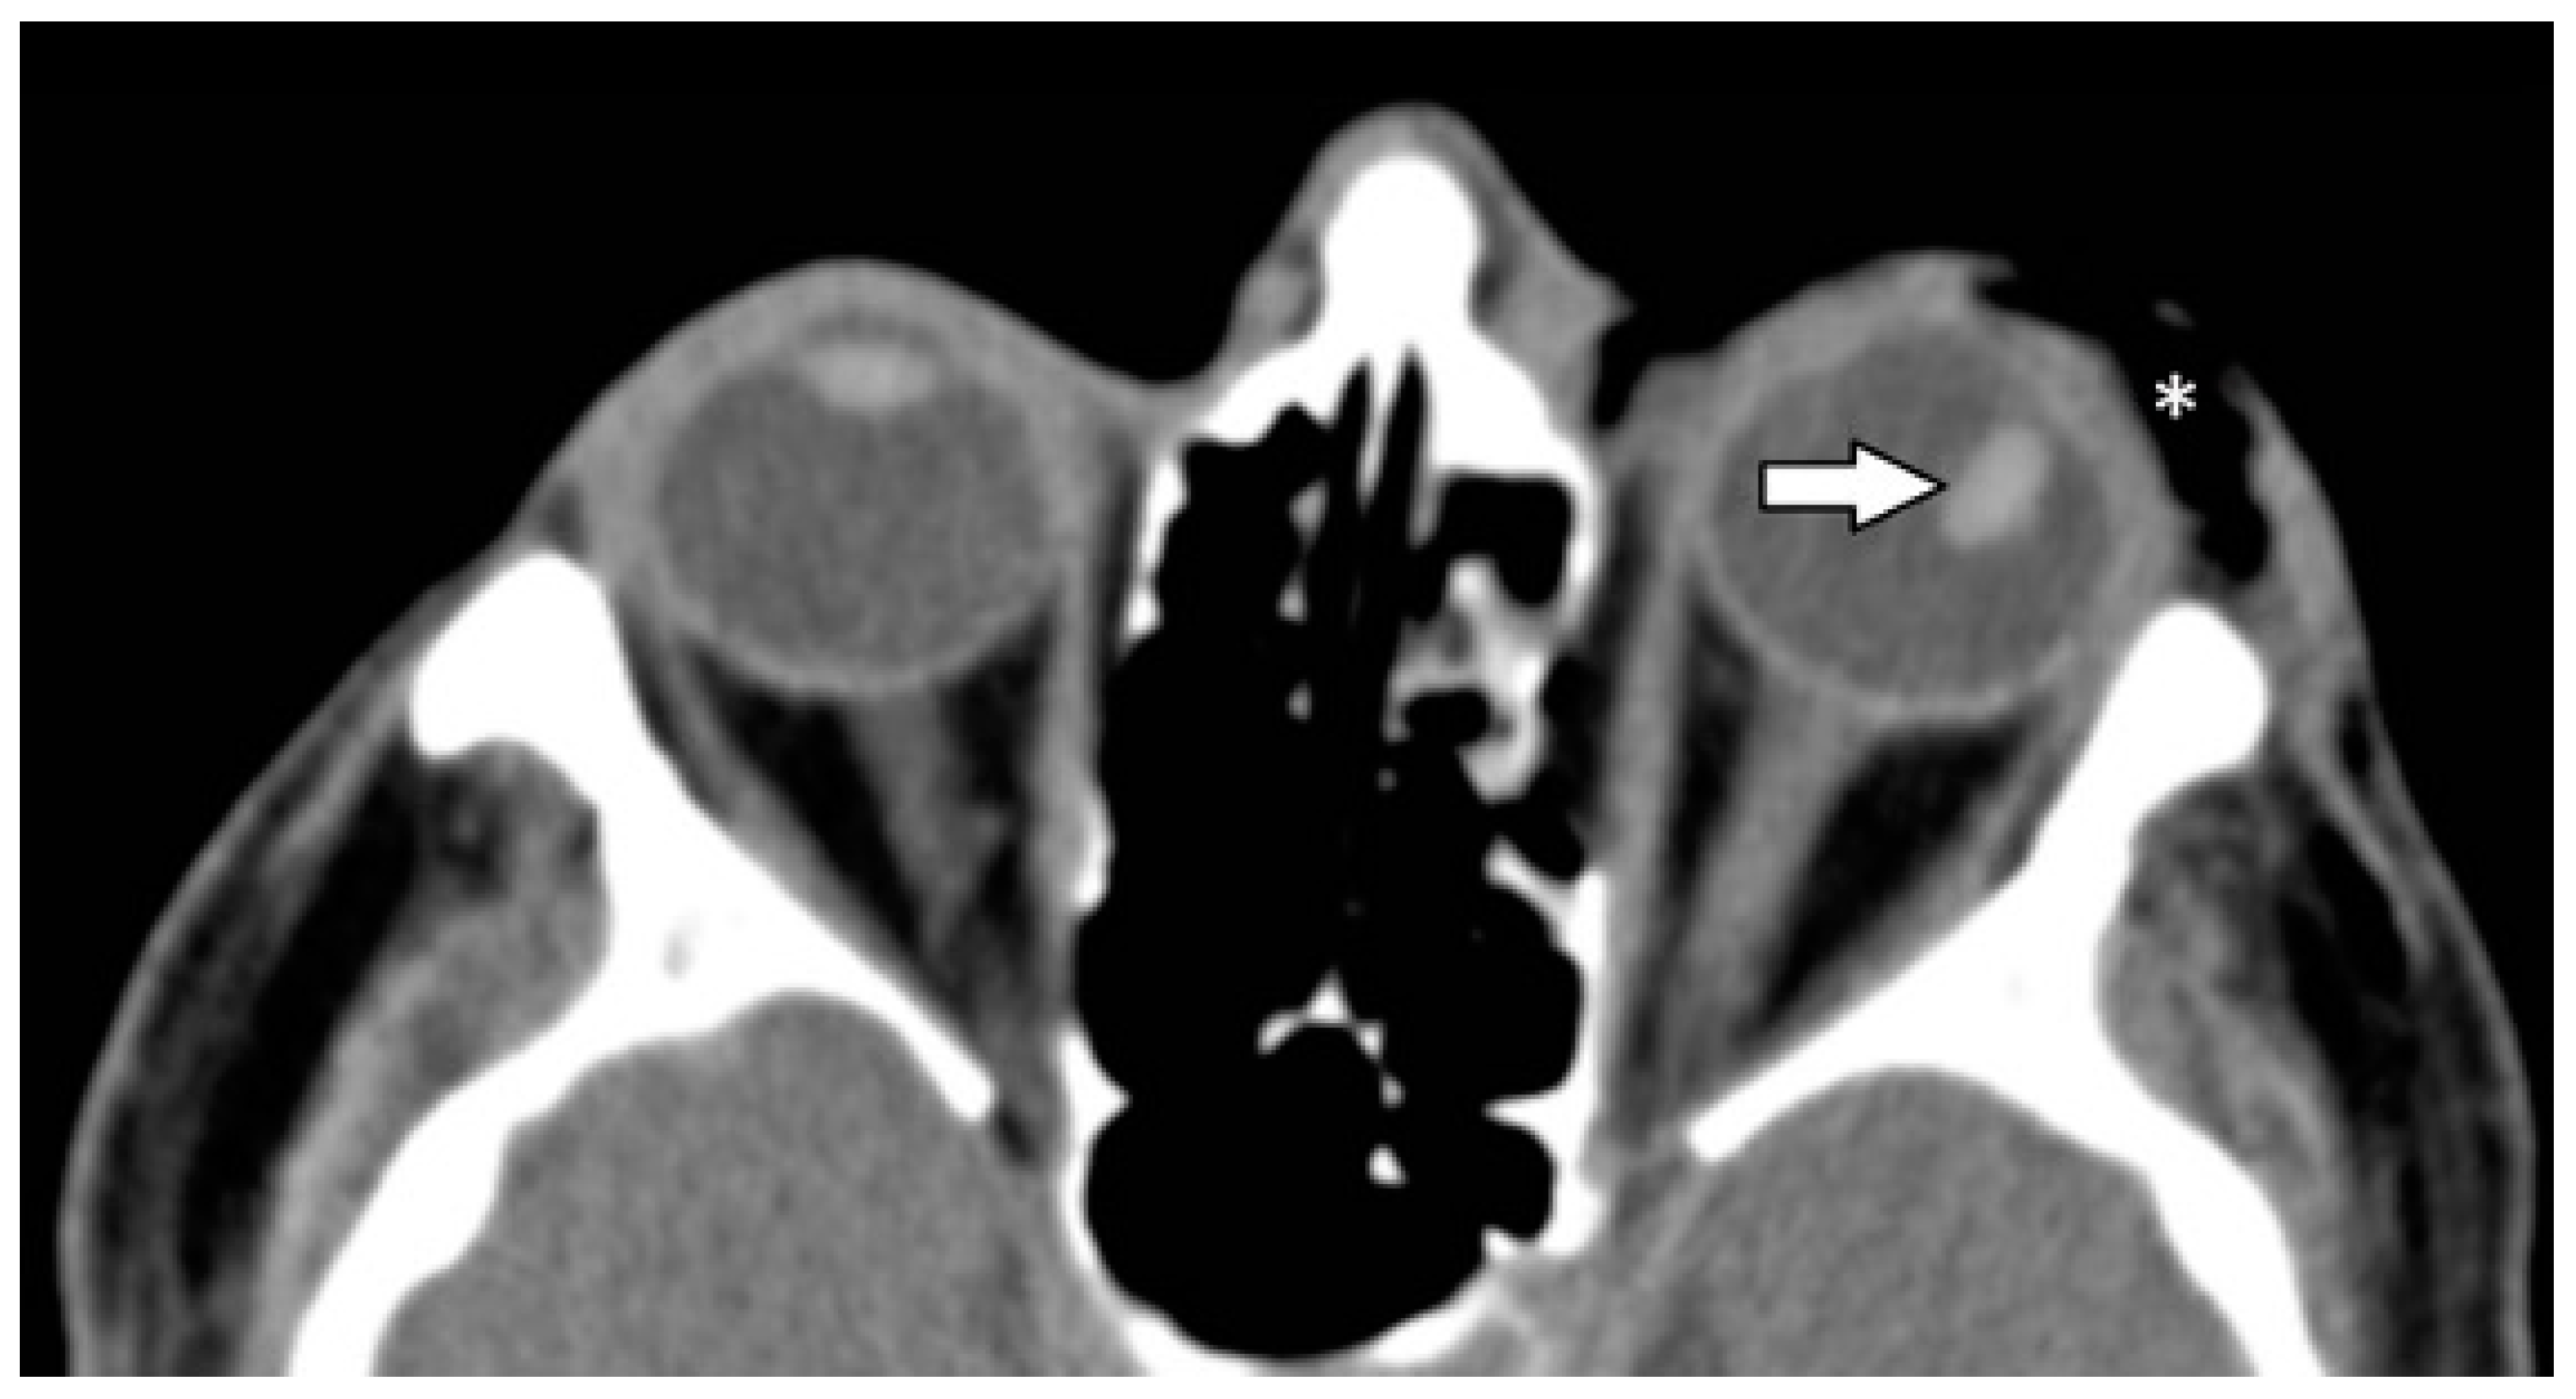

| Ocular globe and lens | 38 (37.6) | |

| Deformed globe or vitreous body | 24 (23.8) | |

| rupture of ocular globe | 7 (6.9) | |

| dislocated lens | 6 (5.9) | |